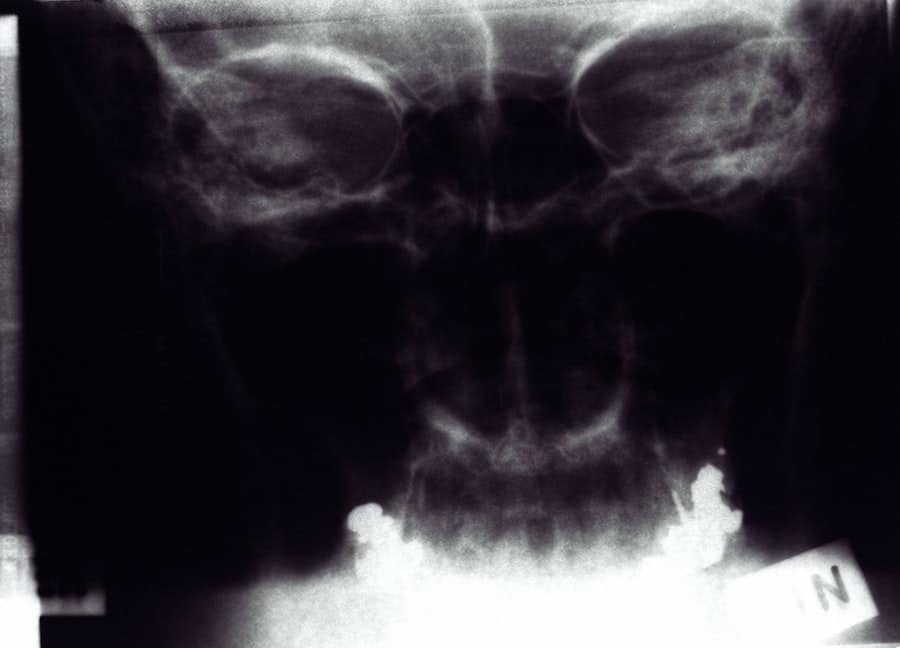

Additionally, if you are seeking rhinoplasty for functional reasons—such as correcting a deviated septum—your insurance may cover part of the costs. Therefore, it’s essential to have a clear understanding of what is included in the total price and to discuss this with your surgeon during your consultation.

What is rhinoplasty?

Rhinoplasty, commonly known as a nose job, is a surgical procedure to reshape or resize the nose for cosmetic or functional purposes.

Does insurance cover the cost of rhinoplasty?

In most cases, rhinoplasty is considered a cosmetic procedure and is not covered by insurance. However, if the procedure is being done for functional reasons, such as to correct a deviated septum or improve breathing, some of the costs may be covered by insurance.